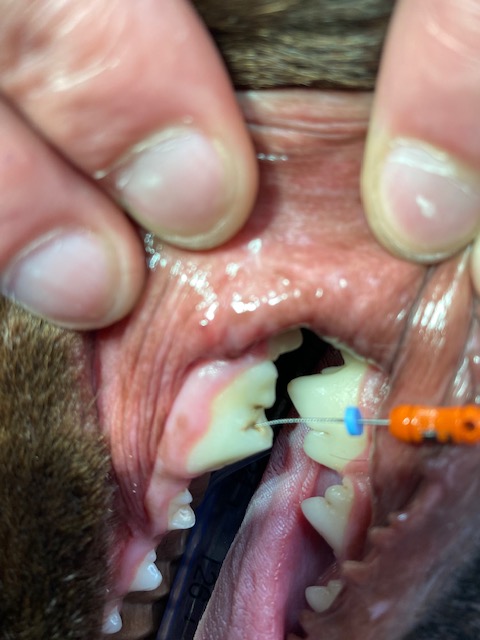

Tooth 208 (upper left premolar) had a complicated crown fracture. When under anesthetic a small pathfinder file was inserted into the pulp. A pre op X-ray showed a slightly lytic circular region around the distal root (black line outlies this). This tooth could have had a root canal operation performed if the owner had wanted to save the tooth, however in this instance an extraction procedure was elected. A maxillary nerve block using bupivicaine was performed, then the tooth was sectioned into 3 and each root removed separately. On the distal root a granuloma can be seen around the apex (this is what was visible on the X-ray). After extraction an X-ray was taken to confirm no root remnants remained and the alveolar bone was smoothed with an oval diamond head bur. The gingival flap sutured closed with simple interrupted 4/0 absorbable suture material with no tension. NSAID pain relief was given post. Antibiotics were not dispensed.